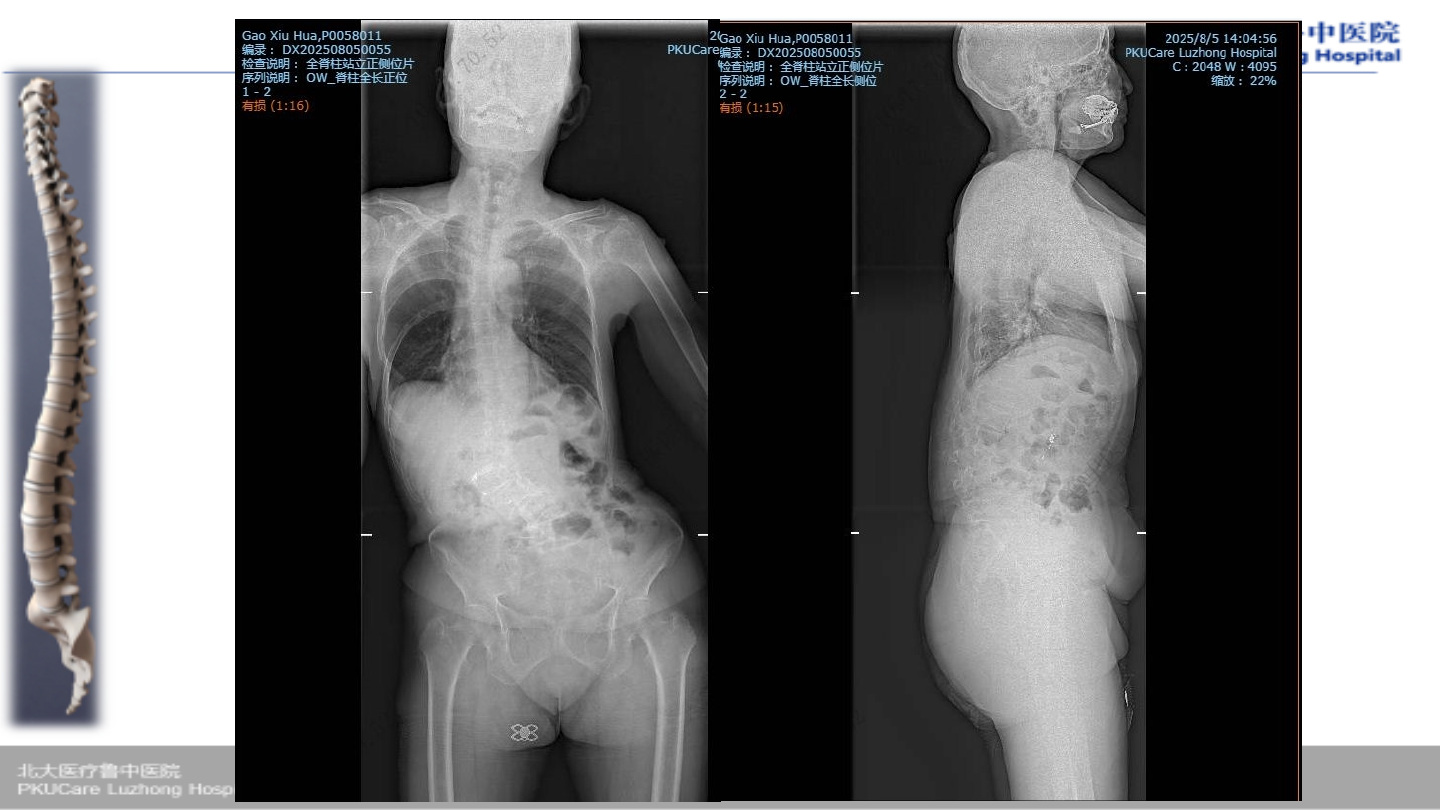

术前腰椎

X-ray